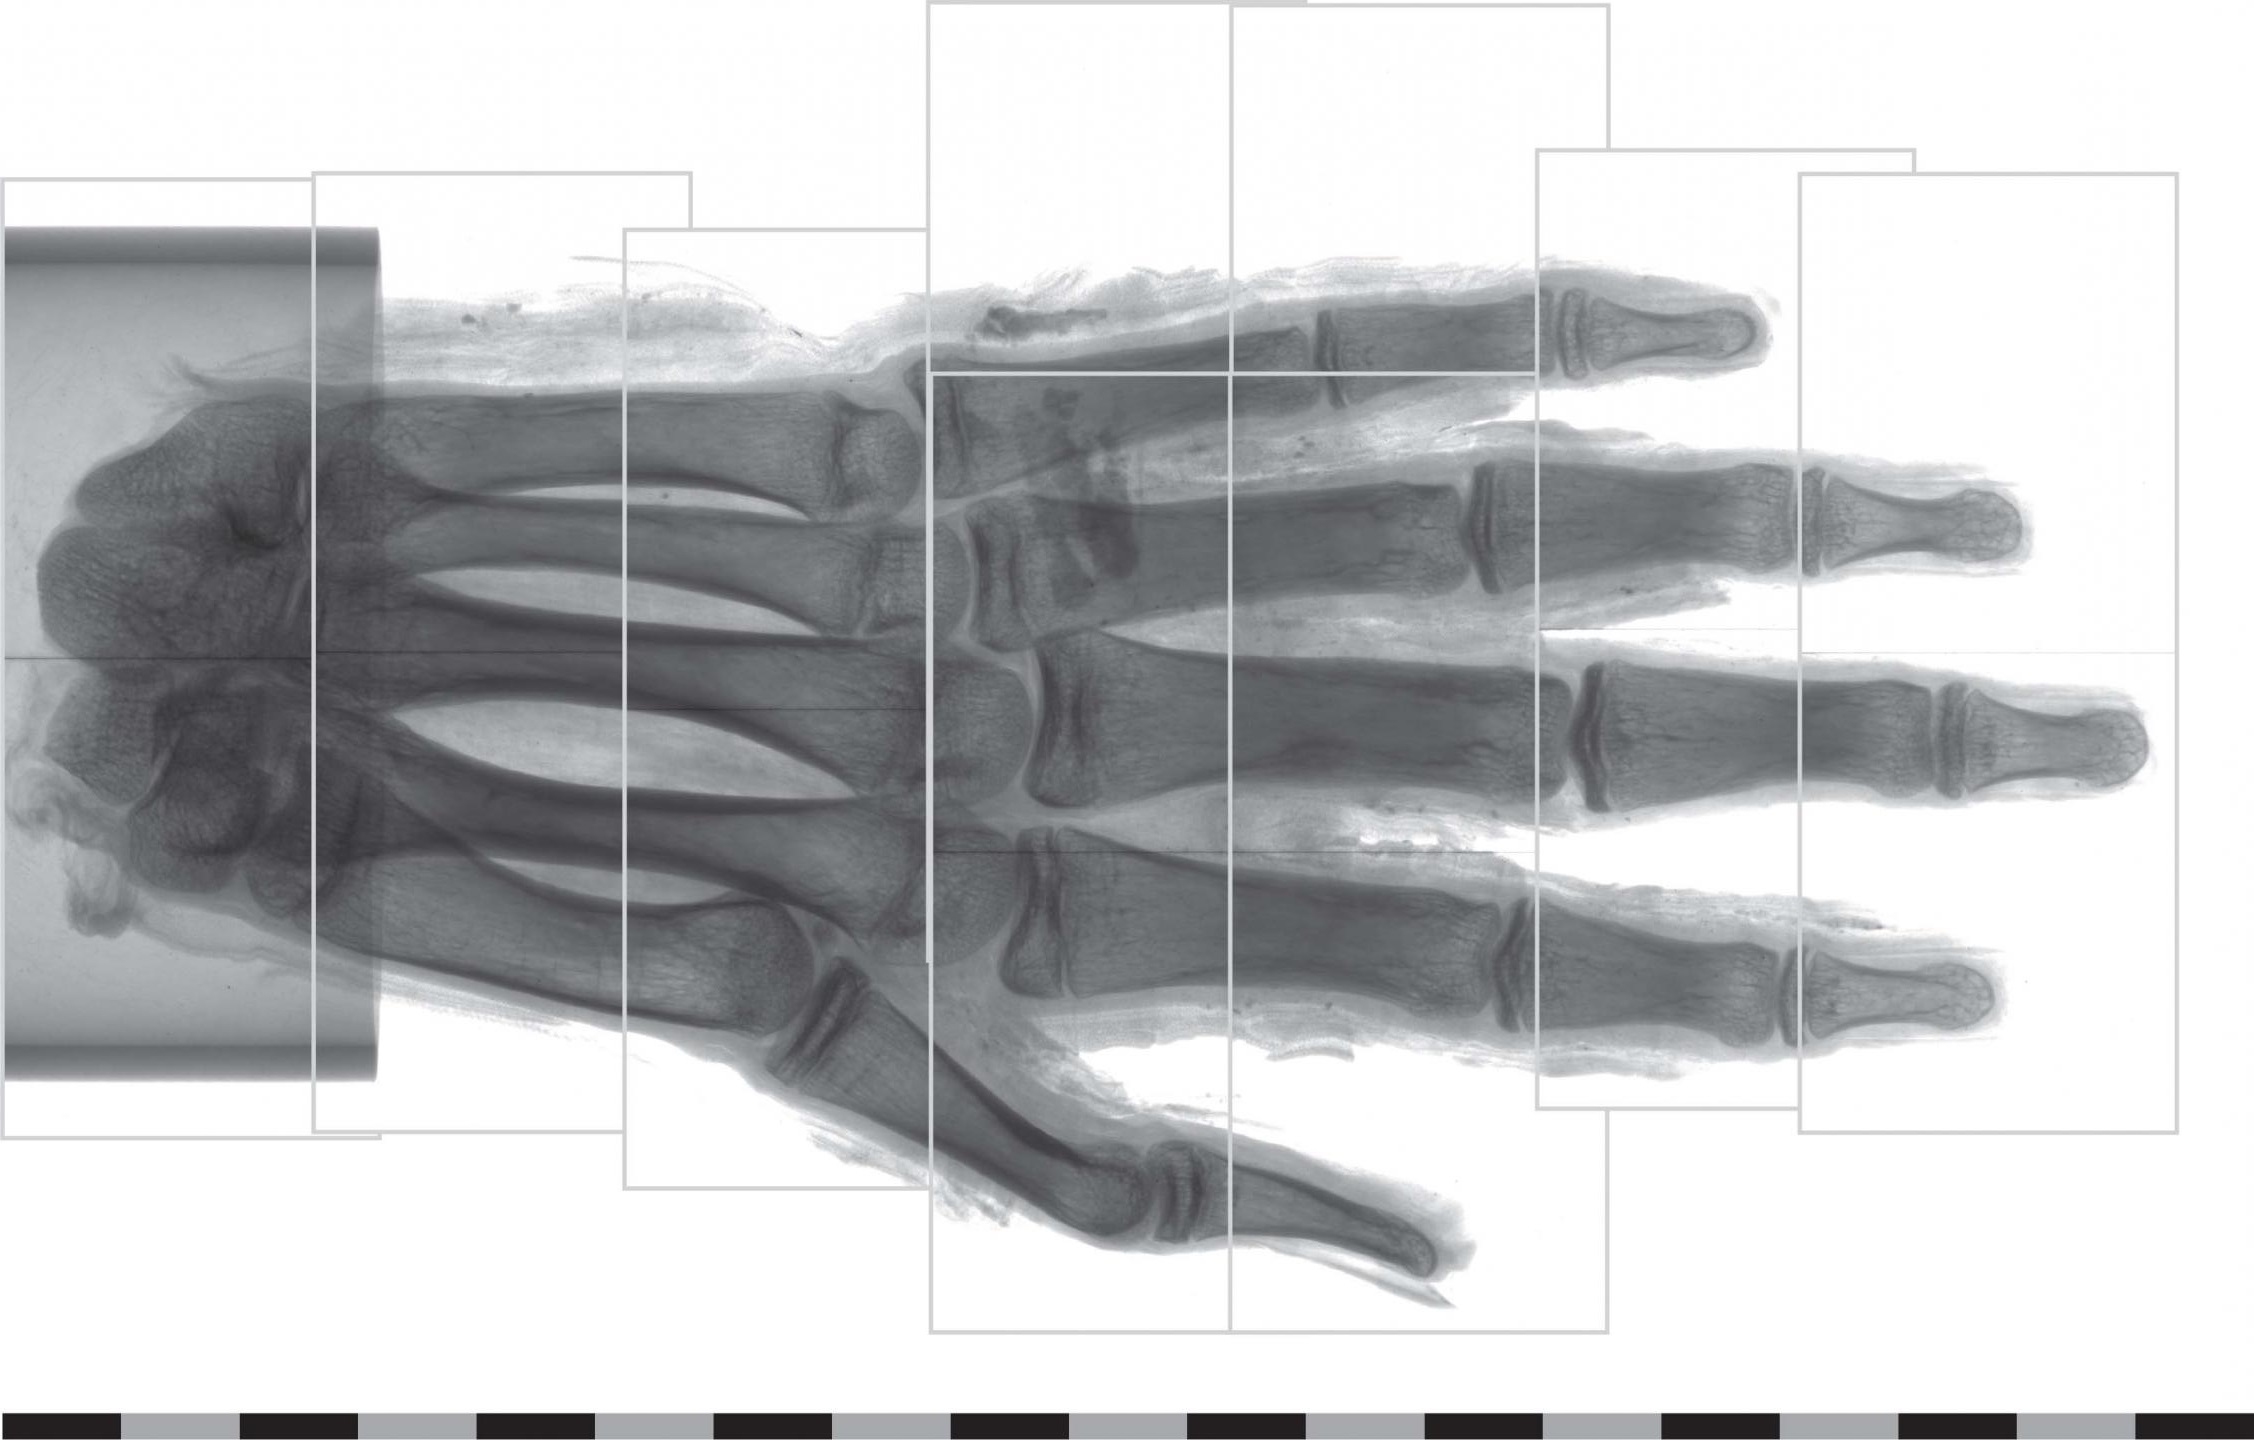

С помощью фазоконтрастной компьютерной томографии исследователи из Швеции смогли до микроскопического уровня визуализировать мягкие ткани руки древнеегипетской мумии. Об этом пишет EurekAlert.

Правая рука, датированная примерно 400 годом до нашей эры, принадлежала жителю Древнего Египта. В конце XIX века ее привезли в Швецию вместе с другими мумифицированными частями тела. Сейчас артефакт хранится в Музее средиземноморских и ближневосточных древностей.

Используя фазоконтрастную компьютерную томографию, ученые изучили всю руку и воссоздали изображение кончика среднего пальца с точностью до от 6-9 микрометров - это немного больше, чем диаметр эритроцита в крови человека. Исследователи смогли увидеть остатки жировых клеток, кровеносных сосудов и нервов. Более того, они даже смогли обнаружить кровеносные сосуды в ногтевом ложе и различить разные слои кожи на кончике пальца.

Для изучения костей и других твердых останков археологи давно используют обычную компьютерную томографию. Однако для визуализации мягких тканей такой способ не подходит, поскольку контраст поглощения излучения в них слишком низкий. Теперь ученые из Швеции доказали, что при работе с мягкими тканями можно использовать фазоконтрастную компьютерную томографию.

"Благодаря фазоконтрастной компьютерной томографии мы смогли воспроизвести изображение древних мягких тканей с точностью, недоступной ранее", - пишут авторы.